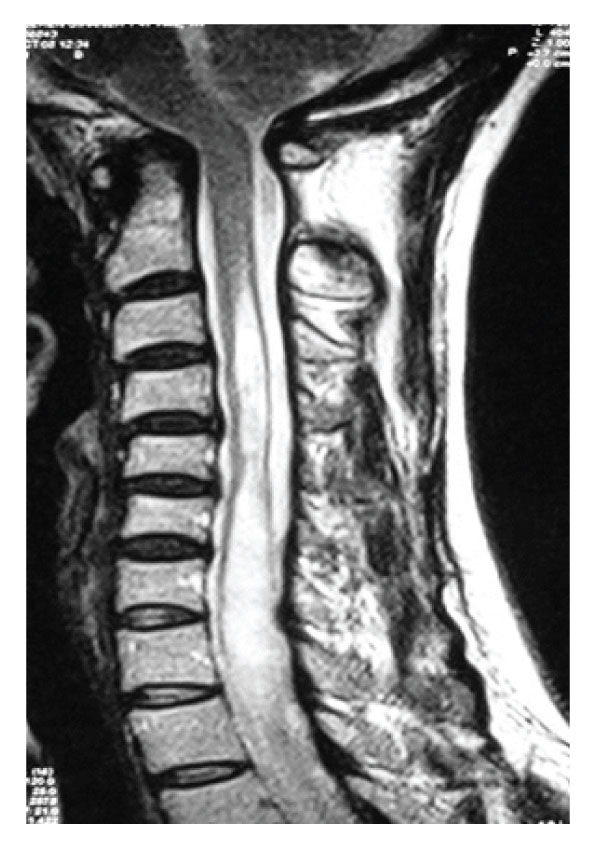

A 45 years old woman was admitted to the hospital with a history of progressive weakness and numbness of the upper extremities. She also had a headache worsening with coughing and gait disturbance. Neurological examination revealed spasticity and weakness of extremities with hyperreflexia. Paresthesia, decreased pain and temperature sensation under C3 level were also observed. Lateral X-rays showed bony abnormality at the craniovertebral junction without basilar invagination. Dynamic

X-ray examination disclosed no instability. Axial CT scans, three dimensional reconstructed CT scans and MRI showed anterior occipitalization of atlas, asymmetrical condyles with hypoplasia of left posterior part of the atlas, rightward deviation of odontoid process and C1-5 syringomyelia without tonsillar herniation [Figure- 1,2,3,4]. Posterior part of the axis was also asymmetrical. There was no appearance of basilar invagination although the tip of the axis was 2 mm superior to the foramen magnum level (McRae line).

Figure 3: A: T2 weighed sagittal MRI demonstrating cervical syringomyelia without tonsillary herniation. B: Postoperative T2 weighted sagittal MRI demonstrating resolution of cervical syringomyelia.

Antero-posterior diameter of foramen magnum was 20 mm; no bony compression to neural structures including odontoid process was detected, however anterior subarachnoid space could not be seen at the level of brain stem. MR angiography disclosed aplasia of left vertebral artery with a nearly normal trace of the right vertebral artery. The patient was treated by a posterior fossa decompression. In the operation, suboccipital craniectomy was performed. The right lamina of the atlas was also removed. Dural surface became expanded and pulsatile suggesting foramen magnum stenosis. CSF flow was observed after opening the dura mater. A large duraplasty was made with dural graft to maintain the CSF flow. Following the decompression and large duraplasty, occipital cervical fusion using C2 laminar screwing was performed. Post-operative period was uneventful, spasticity and weakness of the extremities and hyperreflexia improved. MR examination obtained six months after the operation showed the resolution of the syringomyelia [Figure 3,4].